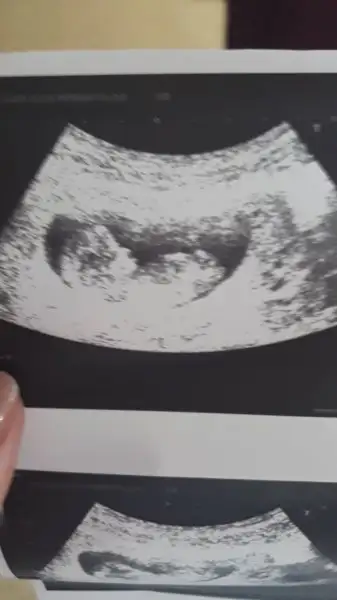

Kizlar buda bnm bebisim suan bir problemimiz yok 2li tarama icon bekliyoruz doktorumuz bir tahminde bulundi birde sizden alabilir miyiz